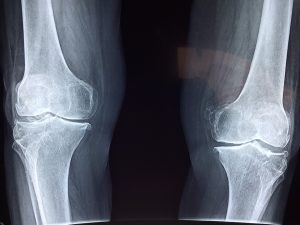

Il ginocchio è un’articolazione costituita da tre ossa, la tibia, il femore e la rotula, oltre al menisco, alla borsa sinoviale e ai legamenti. La funzione delle cartilagini è quella di rendere i movimenti fluidi e continui e di impedire che si crei attrito tra le ossa: la condropatia è una patologia che riguarda qualsiasi tipo di cartilagine presente nel corpo umano.

condropatia rotulea

I sintomi della condropatia rotulea sono il dolore, che tende a peggiorare rimanendo a lungo in piedi e durante l’attività fisica, e gli scricchiolii avvertiti con la flessione ed estensione del ginocchio. Nel caso in cui si avverta un dolore persistente al ginocchio, che non diminuisce neanche dopo il riposo, è opportuno rivolgersi al medico, che valuterà la necessità di effettuare analisi cliniche specifiche o una visita ortopedica, anche se per una prima diagnosi è sufficiente un esame obiettivo e un’anamnesi precisa e accurata. A conferma, il medico potrebbe richiedere alcuni test di diagnostica per immagini, di solito raggi X e risonanza magnetica, o un’artroscopia.